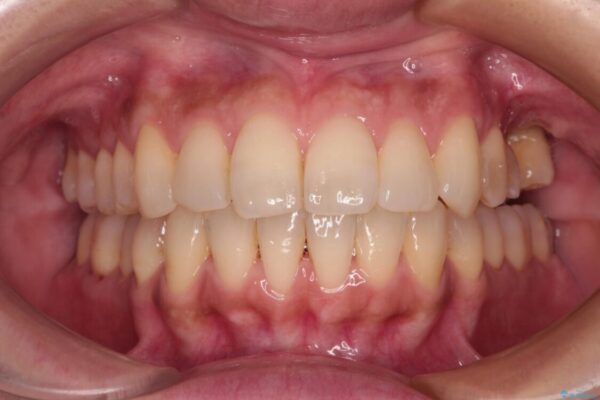

治療後

• インビザラインによる矯正治療と奥歯のインプラント治療 治療後画像

治療後について

歯の傾斜が改善され、インプラントによるクラウンが装着されたことで、物が挟まることもなくなりました。